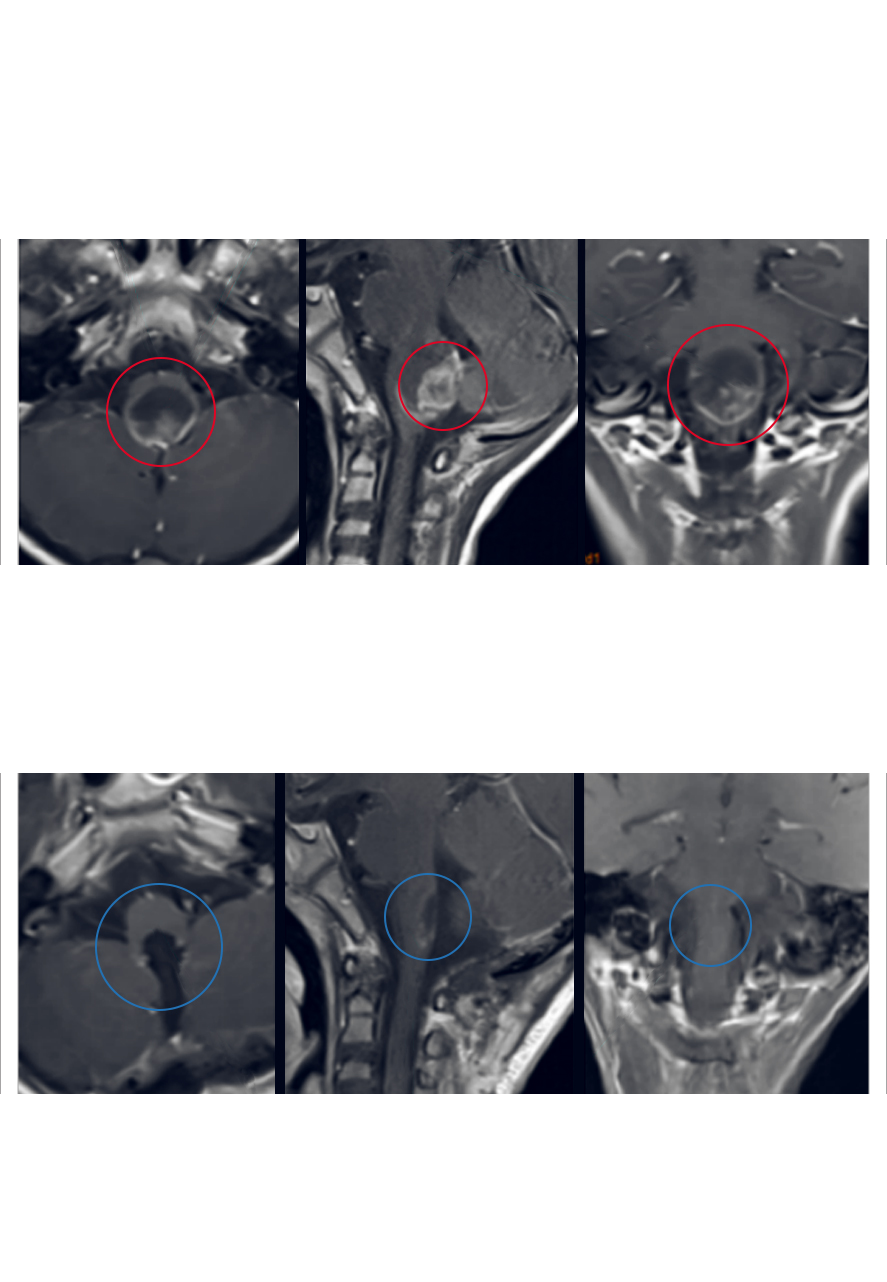

INC案例:脑干间变型室管膜瘤手术、放疗失败,二次手术全切报告

7岁男孩轩轩(化名),3年前出现步态不稳,恶心呕吐。于北京行头颅MR检查,发现脑干肿瘤。当时即在中国行开颅肿瘤切除术,术后症状无好转,术后开始行质子刀放射治疗。病情无明显好转,继续恶化,治疗后一年出现明显吞咽无力、容易呛咳。复查MR见肿瘤增大且明显压迫脑干。